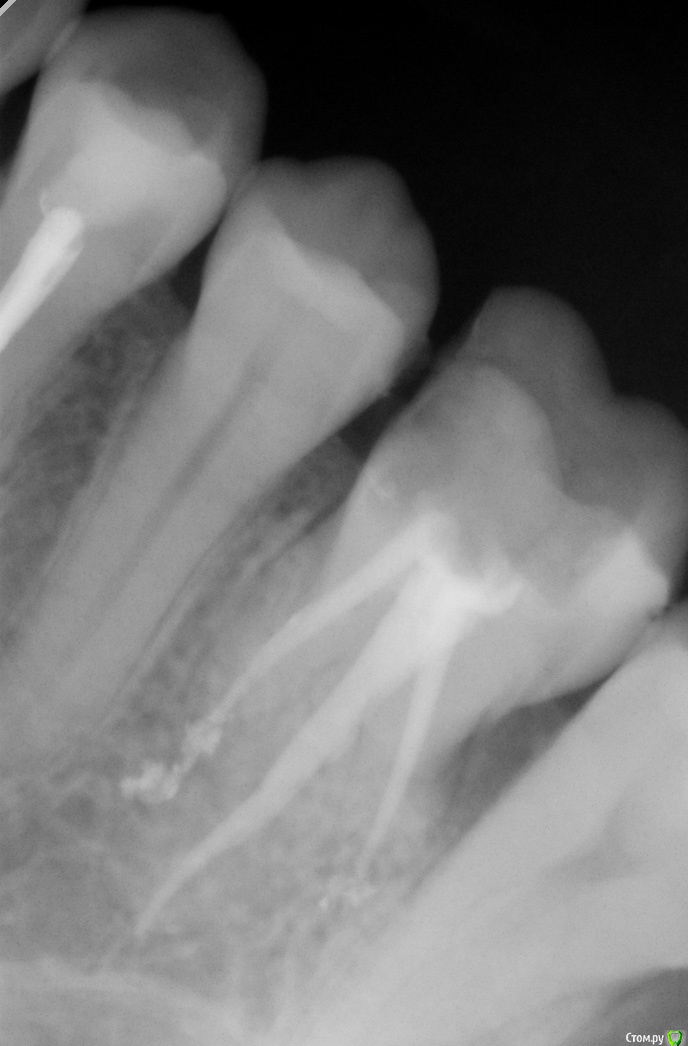

Barbina Опубликовано 30 июня, 2019 Поделиться Опубликовано 30 июня, 2019 Здравствуйте, уважаемые доктора. Помогите пожалуйста. Лечили пульпит в 6 зубе. По итогу спустя время боль не проходит полностью, зуб чувствителен. Лечащий врач проблемы не видит на снимке. Ссылка на комментарий

Barbina Опубликовано 1 июля, 2019 Автор Поделиться Опубликовано 1 июля, 2019 На что реагирует зуб? На температурные раздражители или при накусывании?При накусывание и надавливании есть боль. Во время пользования зубной нити по контактам тоже больно и на холодное реагирует.Ещё скажите, на снимке мне кажется, что пломбировочный материал выходит за пределы корня, я права? Ссылка на комментарий

АнтонТЛТ Опубликовано 1 июля, 2019 Поделиться Опубликовано 1 июля, 2019 Материал немного выведен, но это не критично. Возможно не пройден один канал, советую сделать КТ в области этого зуба.На счёт зубной нити, там контактный пункт не восстановлен между 5 и 6 зубами. Судя по объему разрушения зуб желательно покрыть коронкой или керамической накладкой. 1 Ссылка на комментарий